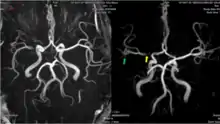

![]() Arterial supply of the brain | |

The leptomeningeal collateral circulation (also known as leptomeningeal anastomoses or pial collaterals) is a network of small blood vessels in the brain that connects branches of the middle, anterior and posterior cerebral arteries (MCA, ACA, and PCA),[1] with variation in its precise anatomy between individuals.[2] During a stroke, leptomeningeal collateral vessels allow limited blood flow when other, larger blood vessels provide inadequate blood supply to a part of the brain.[3]

Leptomeningeal collaterals lie within the leptomeninges, the two deep layers of the meninges called the pia mater and the arachnoid mater.[4] Their diameter has been measured at approximately 300 micrometers,[5] but there is variability between individuals in the size, quantity and location of these vessels, and between either hemisphere within the same subject.[6]

Inter-territorial end to end anastomoses exist between branches of the anterior cerebral artery and middle cerebral artery, the posterior cerebral artery and middle cerebral artery, the anterior cerebral artery and posterior cerebral artery, and the right and left anterior cerebral arteries.[7][8][9][10] Intra-territorial anastamoses connect adjacent arterial branches within the same arterial territory (between two branches of the same middle cerebral artery, for example).[5]